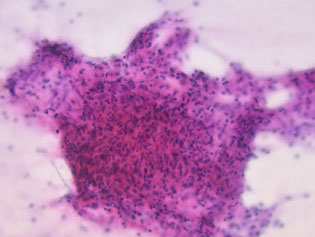

Warthin tumor, with oncocytes, background cyst debris, and chronic inflam

Warthin tumor

- aka Cystadenolymphomatosum or adenolymphoma

Possibly derived from salivary duct remnants trapped in salivary gland LNs; feels doughy

- 2nd MCC salivary gland tumor (up to 1/10 of all)

- 1/10 are multifocal or bilateral

- inc risk in smokers

Micro: oncocytes (abundant granular orange to blue cytoplasm arranged in flat sheets / papillae) scattered and in groups c lymphs and granular debris in background that looks like it contains motor oil

- background nucleated and anucleated squames can be in atypical forms

Tx: resection c preservation of facial n.

Warthin tumor